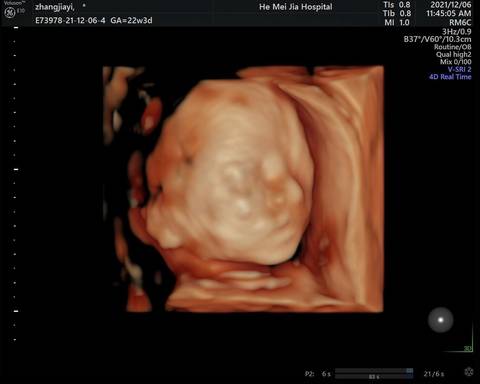

四维顺利通过,很好奇是男孩女孩?有没有帮忙看看,男孩女孩都是宝贝,单纯好奇

你好,检查报告上呢,只能看见宝宝的一个大致轮廓,根本看不到宝宝的性别,建议安心养胎,只要宝宝健康就好。

像女孩子????????

你好。我们是判断不了男宝宝跟女宝宝的,孕期定期检查,我觉得宝宝健康就好的。祝心想事成 。